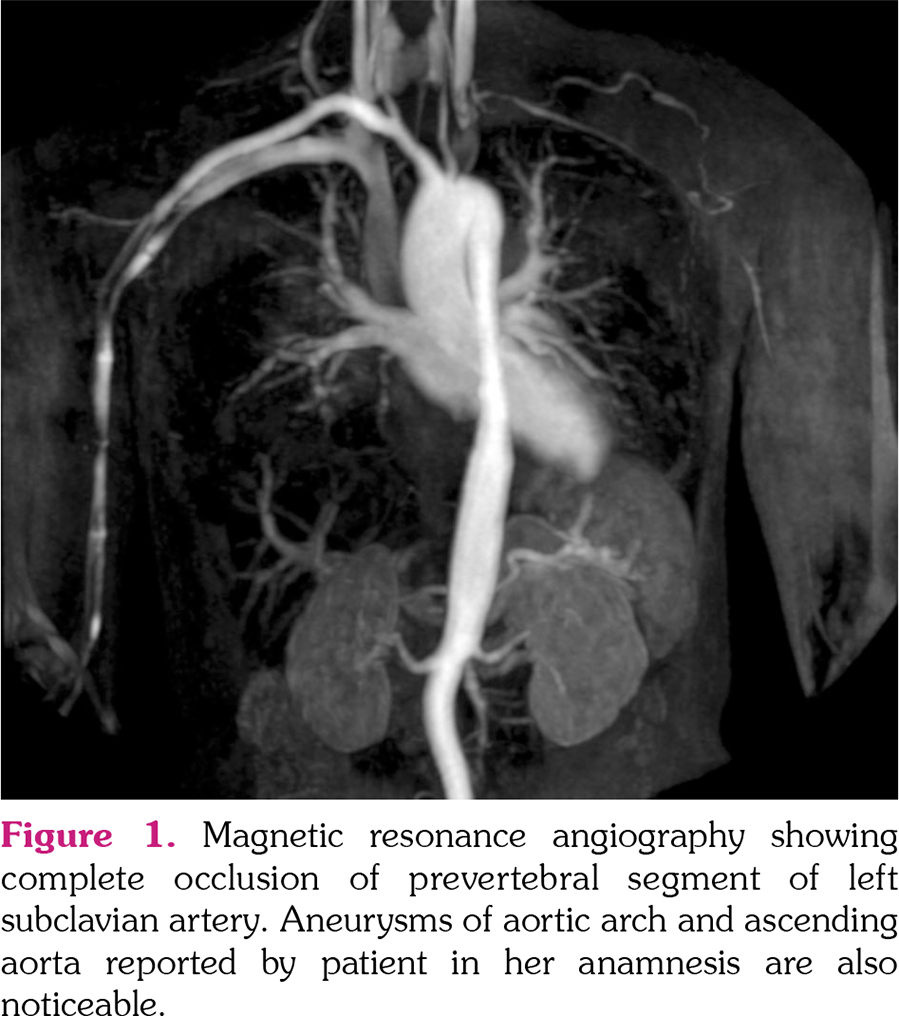

Takayasu arteritis (TAK) is a rare systemic vasculitis affecting large vessels. Disease onset is insidious, with nonspecific early symptoms contributing to a significant diagnostic and therapeutic delay. TAK usually starts in females of reproductive age; hence, planning and management of pregnancy are important issues. Comprehensive evaluation and a multidisciplinary approach to these patients in a tertiary care center can lead to a favorable outcome for the mother and fetus. Unfortunately, still up to one‐ third of TAK patients may be advised against pregnancy by their clinicians.[1] Here, we report the case of a 32‐year‐old female patient (gravida 2, para 1, 52 kg, body mass index 18.6 kg/m[2]) with a history of aortic arch and ascending aorta aneurysm. In 2015, the patient had a term vaginal delivery of a fetus with intrauterine growth restriction (birth weight 1900 g). Postpartum period was complicated by the onset of posterior reversible encephalopathy syndrome, six hours after delivery. Later, neurological follow‐up was negative. She reported to be in good health afterward. In April 2019, she was admitted to Obstetrics and Gynecology departments at 16 weeks of the gestation, complaining of persistent fever unresponsive to paracetamol, paresthesia, and claudication of the left arm and arterial hypertension. Blood tests showed increased acute phase reactants and normal liver and kidney function. A magnetic resonance angiography was carried out, evidencing absence of flow signal in the prevertebral segment of the left subclavian artery with revascularization through the vertebral artery (Figure 1). She was referred to a rheumatologist and TAK was diagnosed (American College of Rheumatology classification criteria were fulfilled because of typical disease onset at ≤40 years, presence of abdominal bruit, left arm claudication, and specific arterial abnormalities).[2] The therapeutic approach consisted of azathioprine 50 mg twice daily and daily prednisone 50 mg with 6.25 mg reduction per week until reaching a maintenance dose of 6.25 mg daily while alpha‐ methyldopa 500 mg twice daily was administered to control hypertension. The subsequent course of pregnancy proceeded without further complications. Fever resolved three days after glucocorticoids initiation whereas acute phase reactants decreased to normal range. The patient underwent elective caesarean section at 37 weeks of gestation. The postoperative course was regular. Arterial hypertension resolved after the birth. She continued to receive azathioprine at the same dose as it was suitable with breastfeeding. At three‐month follow‐up, no disease flare occurred. Successful pregnancy outcomes for both mother and fetus are known for TAK patients.[3] Current evidence indicates that pregnancy does not influence TAK disease activity, although clinicians should be familiar that severe pregnancy‐ related complications, such as hypertension, preeclampsia/eclampsia, prematurity, intrauterine growth restriction as well as inflammatory flares have been reported.[1,4] Of note, their occurrence varies widely between populations;[1] consequently, uncertainties and fear on the part of both patients and counseling physicians may have an impact on family planning in TAK.[1] This case offers food for thought capable of informing TAK management in pregnancy. Concerning counseling, patients should be advised to plan pregnancy during states of low disease activity.